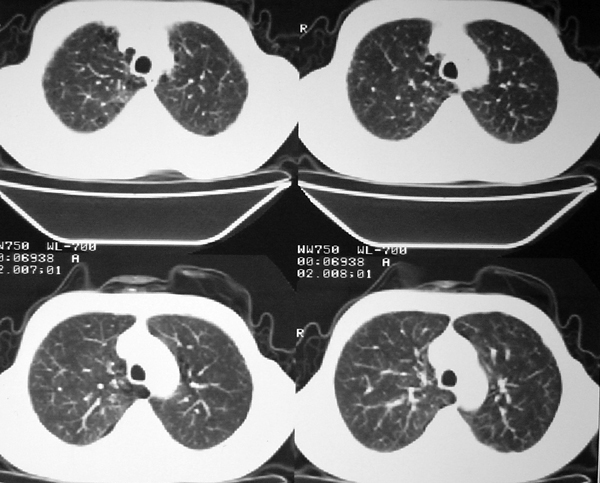

右肺囊实性占位 患者拒绝穿刺活检  近期始终间断性发高烧 使用消炎控制, 左鼻翼部有多发皮肤溃疡

我认为本例肿块内为坏死组织与实性组织混在一起,并夹杂有极低密度气体影,加上肺肿边缘部分呈不规则浅分叶,应该诊断为周围型肺癌。

患者三个月前的ct增强片也显示肿块壁不规则并有明确的壁结节,也支持周围型肺癌的诊断。

右下肺占位性病变,其边缘较光整无明显分叶,似有包膜,邻近胸膜无凹陷征及牵拉征象,包块内见数个大小不等气液面及不规则透亮影,纵隔未见明显淋巴结肿大。结合上次ct检查,考虑:炎性包块或真菌感染包块可能性大,周围型肺癌可能性小。

感谢楼主反馈结果。囊实性肿块,壁厚薄不均,壁结节有明显强化,均支持肺癌诊断。